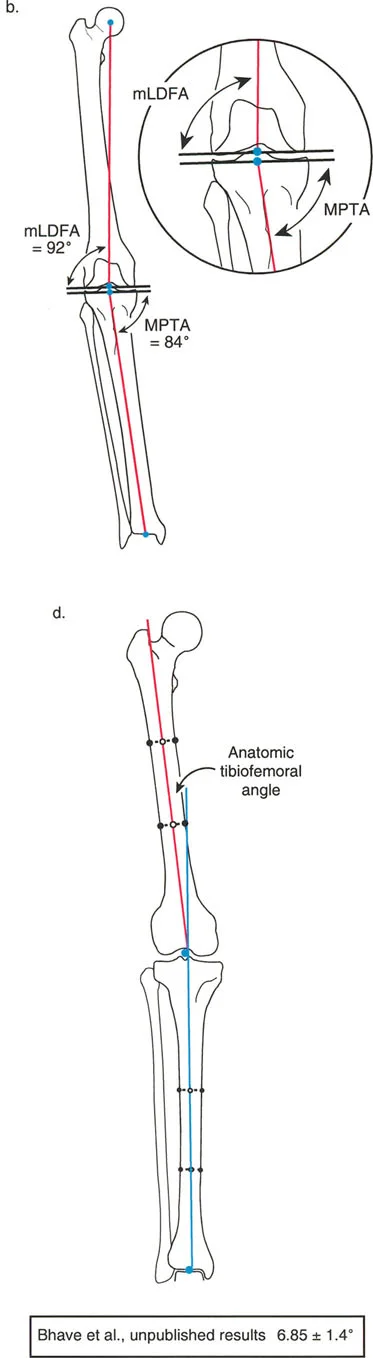

The Anatomic Axis

The anatomic axis represents the mid-diaphyseal line of the bone. It is the line that best bisects the medullary canal.

- Femur: A line drawn through the center of the femoral diaphysis. Because the femur has a natural anterior bow in the sagittal plane and a valgus orientation in the frontal plane, its anatomic axis is distinct from its mechanical axis. The angle between the anatomic and mechanical axes of the femur (AMA) is typically between 5 and 7 degrees, depending on the width of the pelvis and the length of the femur.

- Tibia: A line drawn through the center of the tibial diaphysis. Crucially, in the tibia, the anatomic and mechanical axes are essentially parallel. For practical surgical planning purposes in the frontal plane, they are considered collinear.

- aLDFA (anatomic Lateral Distal Femoral Angle): The angle between the anatomic axis of the femur and the distal femoral joint line on the lateral side.

- Normal Value: 81° (Range: 79° - 83°)